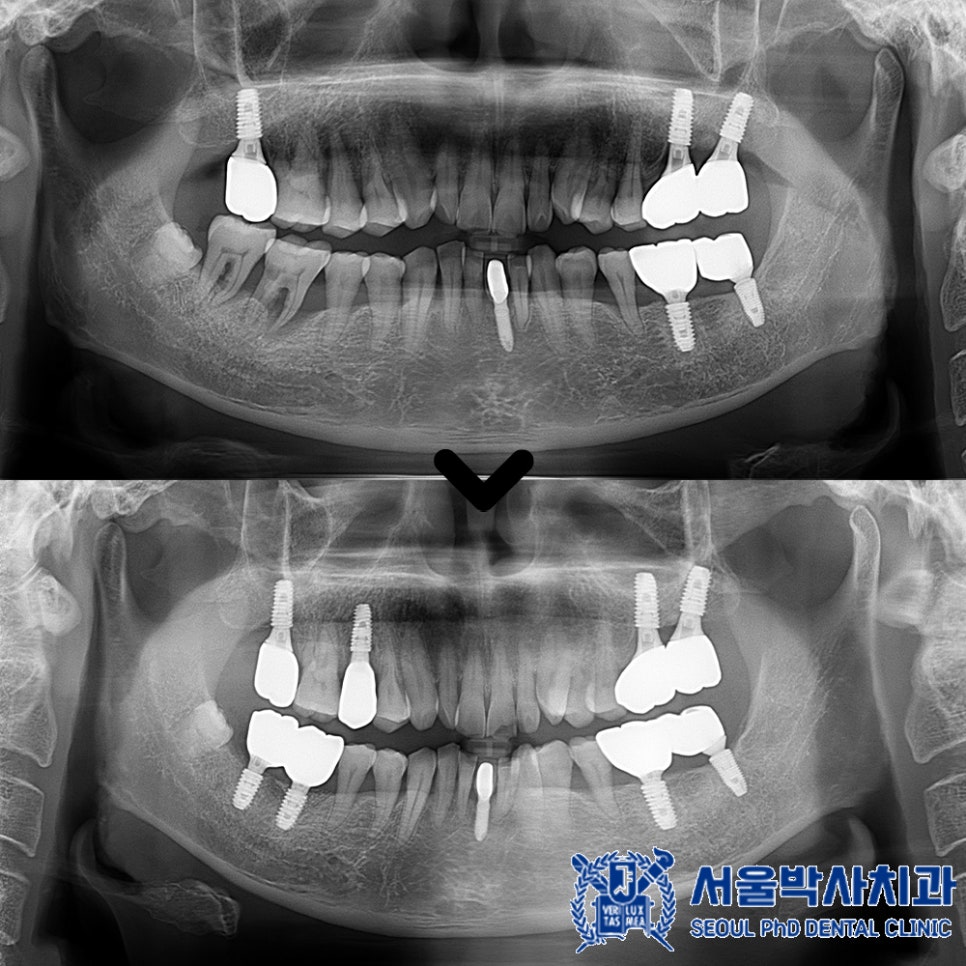

수술 후 약 3개월간의

치유기간을 거친 후,

최종 임플란트 보철물을

세팅해드렸습니다.

서울박사치과에는

원내 기공소가 있기 때문에

더욱 정밀하게 보철물을

제작할 수 있는데요.

특히 10년 이상의 경력을 가진

전문 기공사가 상주하고 있어

퀄리티 높은 보철물 제작이 가능합니다.

또한 맞춤형 지대주를 사용하여

음식물이 끼임이 적고

환자 구강 구조에 완벽히 맞춰

보철을 제작하고 있습니다.

내구성이 높은 재료를 사용하여

오래 사용할 수 있으며,

자연치아처럼 심미적인 면도 우수합니다.